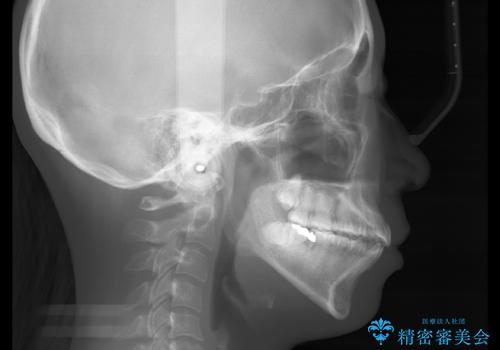

- 前歯を後ろへ下げることを主訴に来院された患者様です。

10代の時に非抜歯でワイヤー矯正をしていました。

口元の突出感の改善や歯の移動量などを考慮し、抜歯を伴うワイヤー矯正での治療を選択しました。

抜歯を行うことで前歯を後ろへ下げるスペースを獲得し、口元の突出感や歯のガタつきを改善していきました。